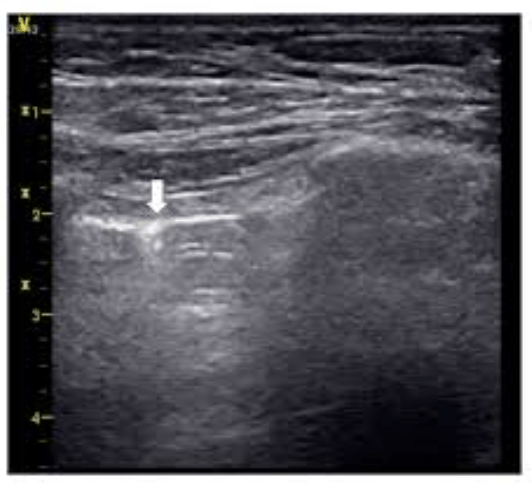

This US fidning on skin US

What is cobblestoning?